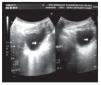

Su evolución posquirúrgica fue favorable. Se mantuvo con profilaxis antimicrobiana por tres meses, con estudios de control sin alteraciones (examen general de orina, urocultivo, cistograma retrógrado). Las Figuras 3 y 4 muestran las imágenes de ultrasonido y cistograma retrógrado posoperatoriamente, donde ya no hay evidencia del divertículo.

Figura 3.Ultrasonido posquirúrgico sin evidencia de divertículo.